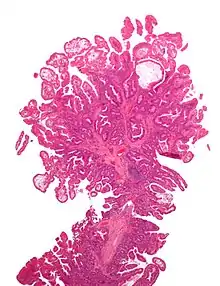

| Type | Risk of containing malignant cells | Histopathology | Image | |

| Hyperplastic polyp | 0% | No dysplasia.[10]

|

![]() | |